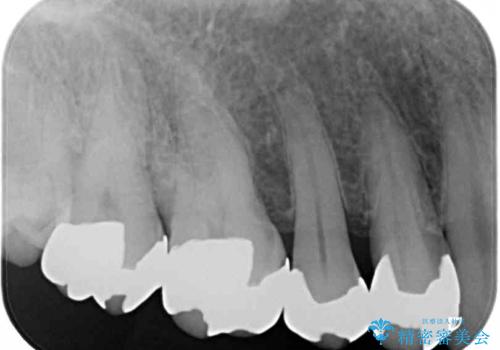

- 奥歯の銀歯をセラミックの白い歯にして、しみる症状も改善したいとのことで来院された患者様です。

知覚過敏の症状が強い歯と、銀歯の範囲や銀歯の下のむし歯が大きい歯は、インレー修復では対応が難しいためオールセラミッククラウンで、インレー修復で対応が可能な歯ではセラミックインレーにて修復することとしました。